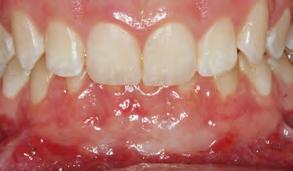

Paciente masculino de 23 años de edad el cual acudió al servicio de Odontología para valoración odon tológica anual como parte del exa men médico anual quien refiere a Cirugía Maxilofacial del Hospital Regional Naval de Acapulco (Figura 1). El paciente mencionó inicio de padecimiento con aumento de volu men y úlcera en paladar blando de 6 meses de evolución con salida de

material purulento (Figura 1). Negó crónico degenerativo, alérgicos y res to de antecedentes sin importancia. Se solicitaron estudios de laboratorio prequirúrgicos los cuales se encontra ron dentro de los parámetros norma les.

Paciente Figura 1. Fotografía clínica frontal. Figura 2. Con aumento de volumen y úlcera en paladar blando.